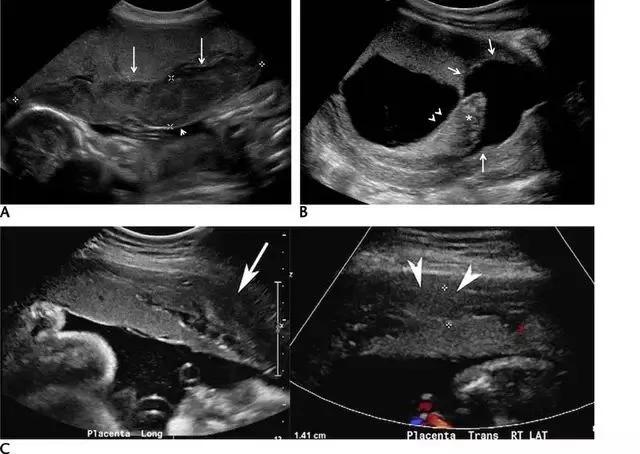

胎盘早剥指胎盘尚未成熟即与子宫壁分离开来的状况,是晚期妊娠出血的主要原因。胎盘前早剥发生于胎盘与羊水之间的绒毛膜板下,较其它类型的早剥少见;胎盘后血肿继发于蜕膜小动脉的破裂,导致血液在胎盘基底板与子宫壁之间积聚,可造成胎盘基底板坏死及绒毛梗死,导致严重不良妊娠结局。

胎盘后复合体通常厚约 1~2 mm,由子宫胎盘血管及肌层所构成;如果超声发现此处增厚,应疑及胎盘后血肿。急性期的血肿回声较胎盘回增强或与之相同,一周后变为低回声,两周后可变为无回声(图 14)。

图 14 示胎盘早剥:A 为孕 24 周时的胎盘横切面,胎盘表面(长箭头)与羊膜(短箭头)之间可见一个较大的低回声区,此为胎盘前早剥。B 为孕 11 周的子宫矢状面,可见胎盘后的慢性无回声出血灶(长箭头),并延伸至绒毛下空间(短箭头),星号示出血灶导致胎盘边缘抬起。C 为另一孕 27 周伴无痛性阴道出血患者的子宫矢状面及横切面,长、短箭头所指回声为胎盘后的亚急性出血灶

超声对于急性或超急性胎盘早剥的检出并不敏感,尤其当出血灶局限于胎盘后方,此时胎盘外膜完整、出血灶处于隐蔽状态。胎盘后出血常常预示胎儿出生后的状况差,因而应积极处理这种出血。